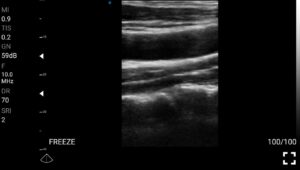

Παραδείγματα

Ολες οι παραπάνω απεικονιστικές εξετάσεις έχουν ληφθεί από φορητή συσκευή όπως: Apple Iphone, Tablet, Samsung Mobile Phones και διάφορες άλλες φορητές συσκευές.

Παραδείγματα Video